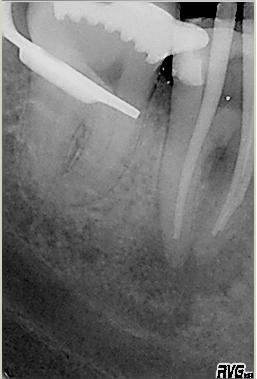

Erste Kontrolle direkt nach Wurzelfüllung mit vertikaler Kondensation erwärmter Guttapercha mit System B und Obtura 2. Man beachte die dreidimensionale Füllung der Seitenkanäle der mesialen Wurzel

Kontrolle

Kontrolle nach adhäsivem Aufbau ungefähr zwei mm unterhalb der Kanaleingänge im November 2002